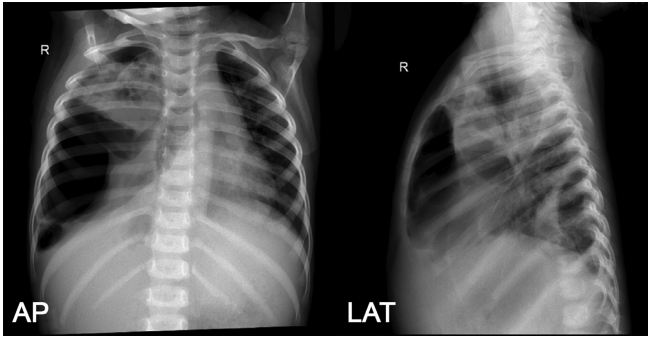

患者因贫血接受输血,给予氨苄西林舒巴坦250mg/6小时和美罗培南400mg/8小时。一周后复查胸片,右肺实变伴多发性肺大泡,右中下肺不张,右肺积水,左胸腔积液(图4)。WSD产量增加到30至50毫升。最初计划对患儿行开胸肺大泡切除术和肺叶切除术。但由于患者全身情况持续恶化,手术被推迟。

图4. 入院第8天AP胸片和侧位投影复查,显示右半胸多发大泡和水气胸,肺塌陷,右肺上叶有多个空洞